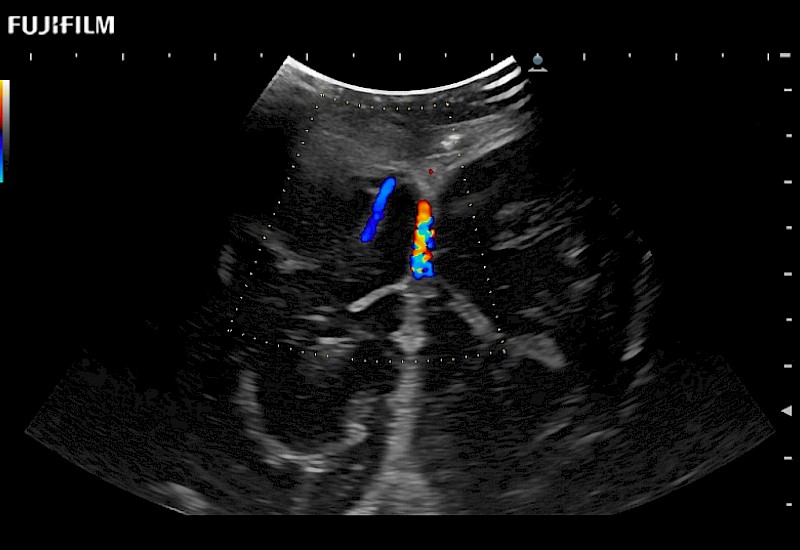

Exclusive 10mm side‐fire linear array transducer with 2.87mm diameter is ideal for real‐time visualization through and behind structures and instant, scalable definition of anatomy and vascularity including the ability to delineate and define tumor margins.

Main Specifications: